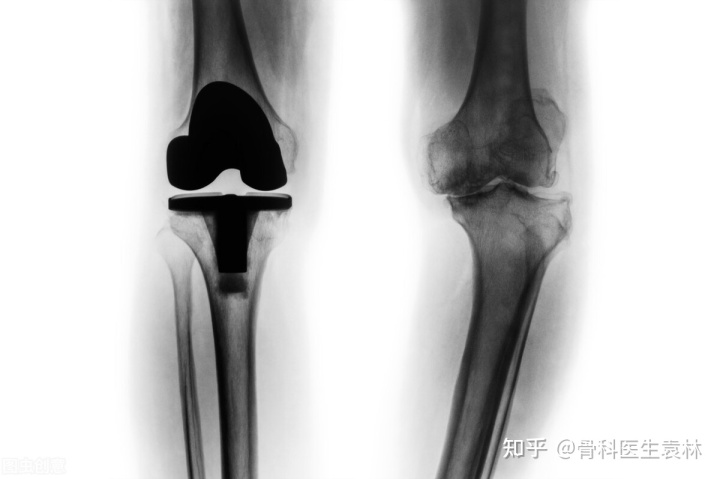

中晚期的膝关节骨性关节炎,保守治疗通常难以得到满意的效果,尤其是晚期的骨关节炎,通常需要实行人工全膝关节置换术来帮助治疗。

4、重建治疗:患者病情严重,手术修复性治疗无效时进行手术关节重建治疗,包括关节置换术、关节融合术、截骨术等。手术重建治疗为终末期膝关节炎治疗的有效方案,能有效缓解关节疼痛,恢复关节活动功能。